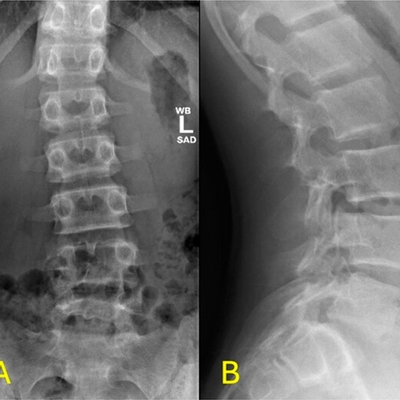

Click on an image below to view more info.